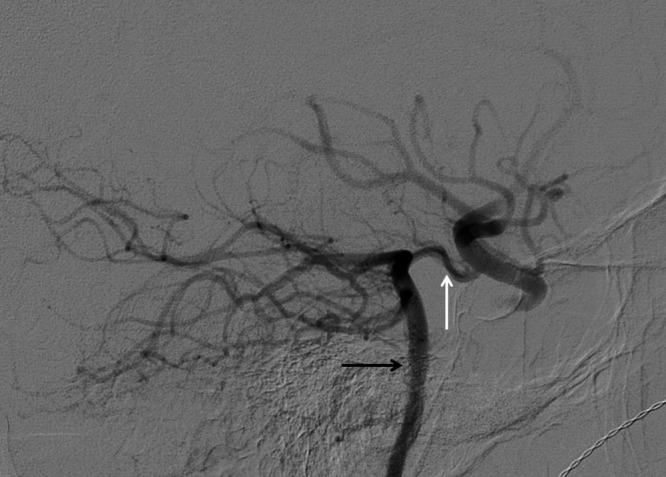

A teenage boy who had been stabbed in the neck presented with an extracranial traumatic functional carotid artery occlusion that could not be crossed in an antegrade fashion. Endovascular repair depends on obtaining catheter access proximal and distal to an injury within the true lumen.

The occlusion was treated with flossing technique via the posterior communicating artery. After successful recanalization from a retrograde approach, the carotid artery occlusion was treated with a covered stent.